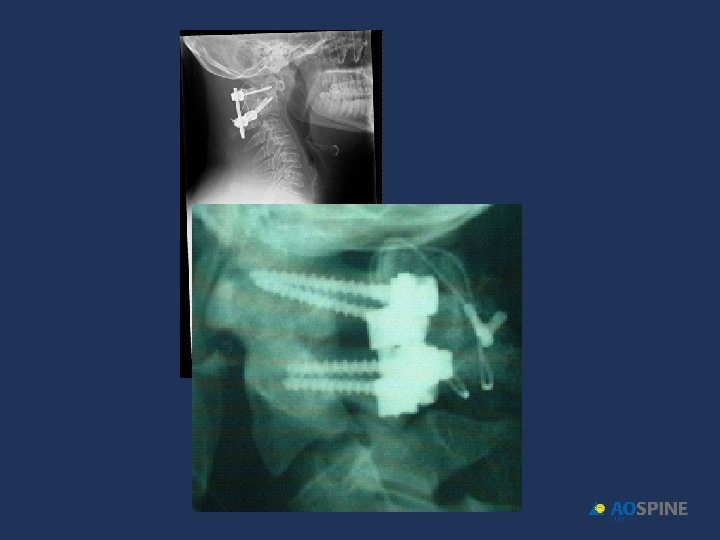

HANGMAN´S FRACTURES surgical treatment C 2 C 3 DISC DISRUPTION INHABILITY TO MANTAIN ALIGNMENT NON UNION POSTERIOR FUSION C 1 C 3 ANTERIOR DISCECTOMY + FUSION C 2 C 3 POSTERIOR C 2 PEDICLE SCREWS

HANGMAN´S FRACTURES INSTABILITY: ANTERIOR DISPLACEMENT C 2 C 3 > 50%

Francis grade V